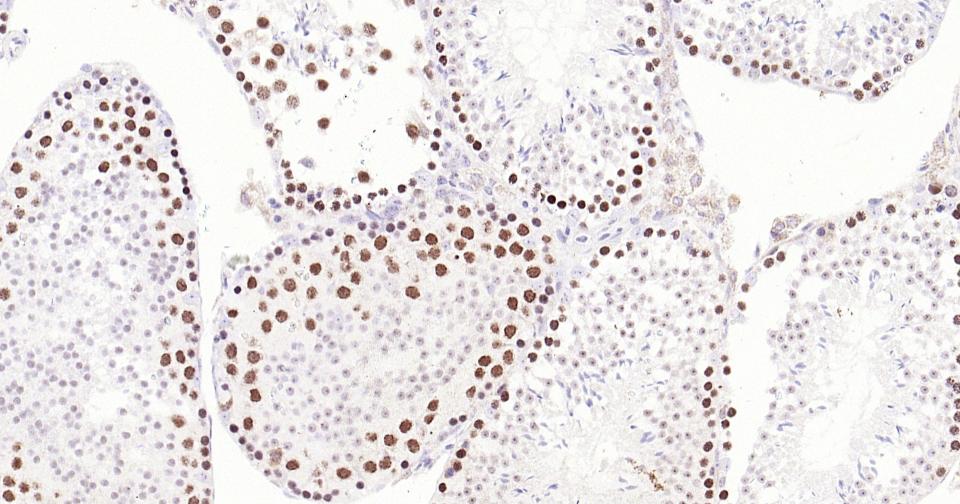

Paraformaldehyde-fixed, paraffin embedded Human Testicles; Antigen retrieval by boiling in sodium citrate buffer (pH6.0) for 15 min; Antibody incubation with TOP2A Monoclonal Antibody, Unconjugated(bsm-61077R) at 1:400 overnight at 4°C, followed by conjugation to the SP Kit (Rabbit, SP-0023) and DAB (C-0010) staining.